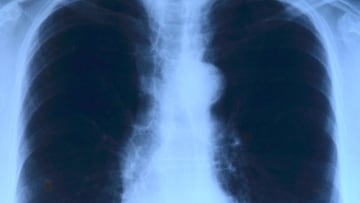

Científicos resuelven una de las causas del cáncer de pulmón más comunes y no tiene nada que ver con el tabaco

Cuanta mayor es la contaminación atmosférica, mayor riesgo existe de desarrollar un cáncer de pulmón, según un estudio.

¿Por qué cada vez más personas no fumadoras desarrollan un cáncer de pulmón? Un estudio internacional publicado este miércoles en la revista Nature cree que la contaminación atmosférica es la respuesta. Según el informe, los no fumadores tienen en su ADN “firmas mutacionales” y daños similares a los que poseen las personas fumadoras.

Los resultados del estudio muestran una conexión férrea entre la contaminación atmosférica y el riesgo de desarrollar un cáncer de pulmón. Según explica El País, el 99% de la población mundial respira niveles muy altos de partículas de 2,5 micras de diámetro producidas por la combustión de combustibles fósiles. Estas partículas pueden entrar hasta los lugares más profundos de las vías respiratorias e introducirse en el riego sanguíneo.